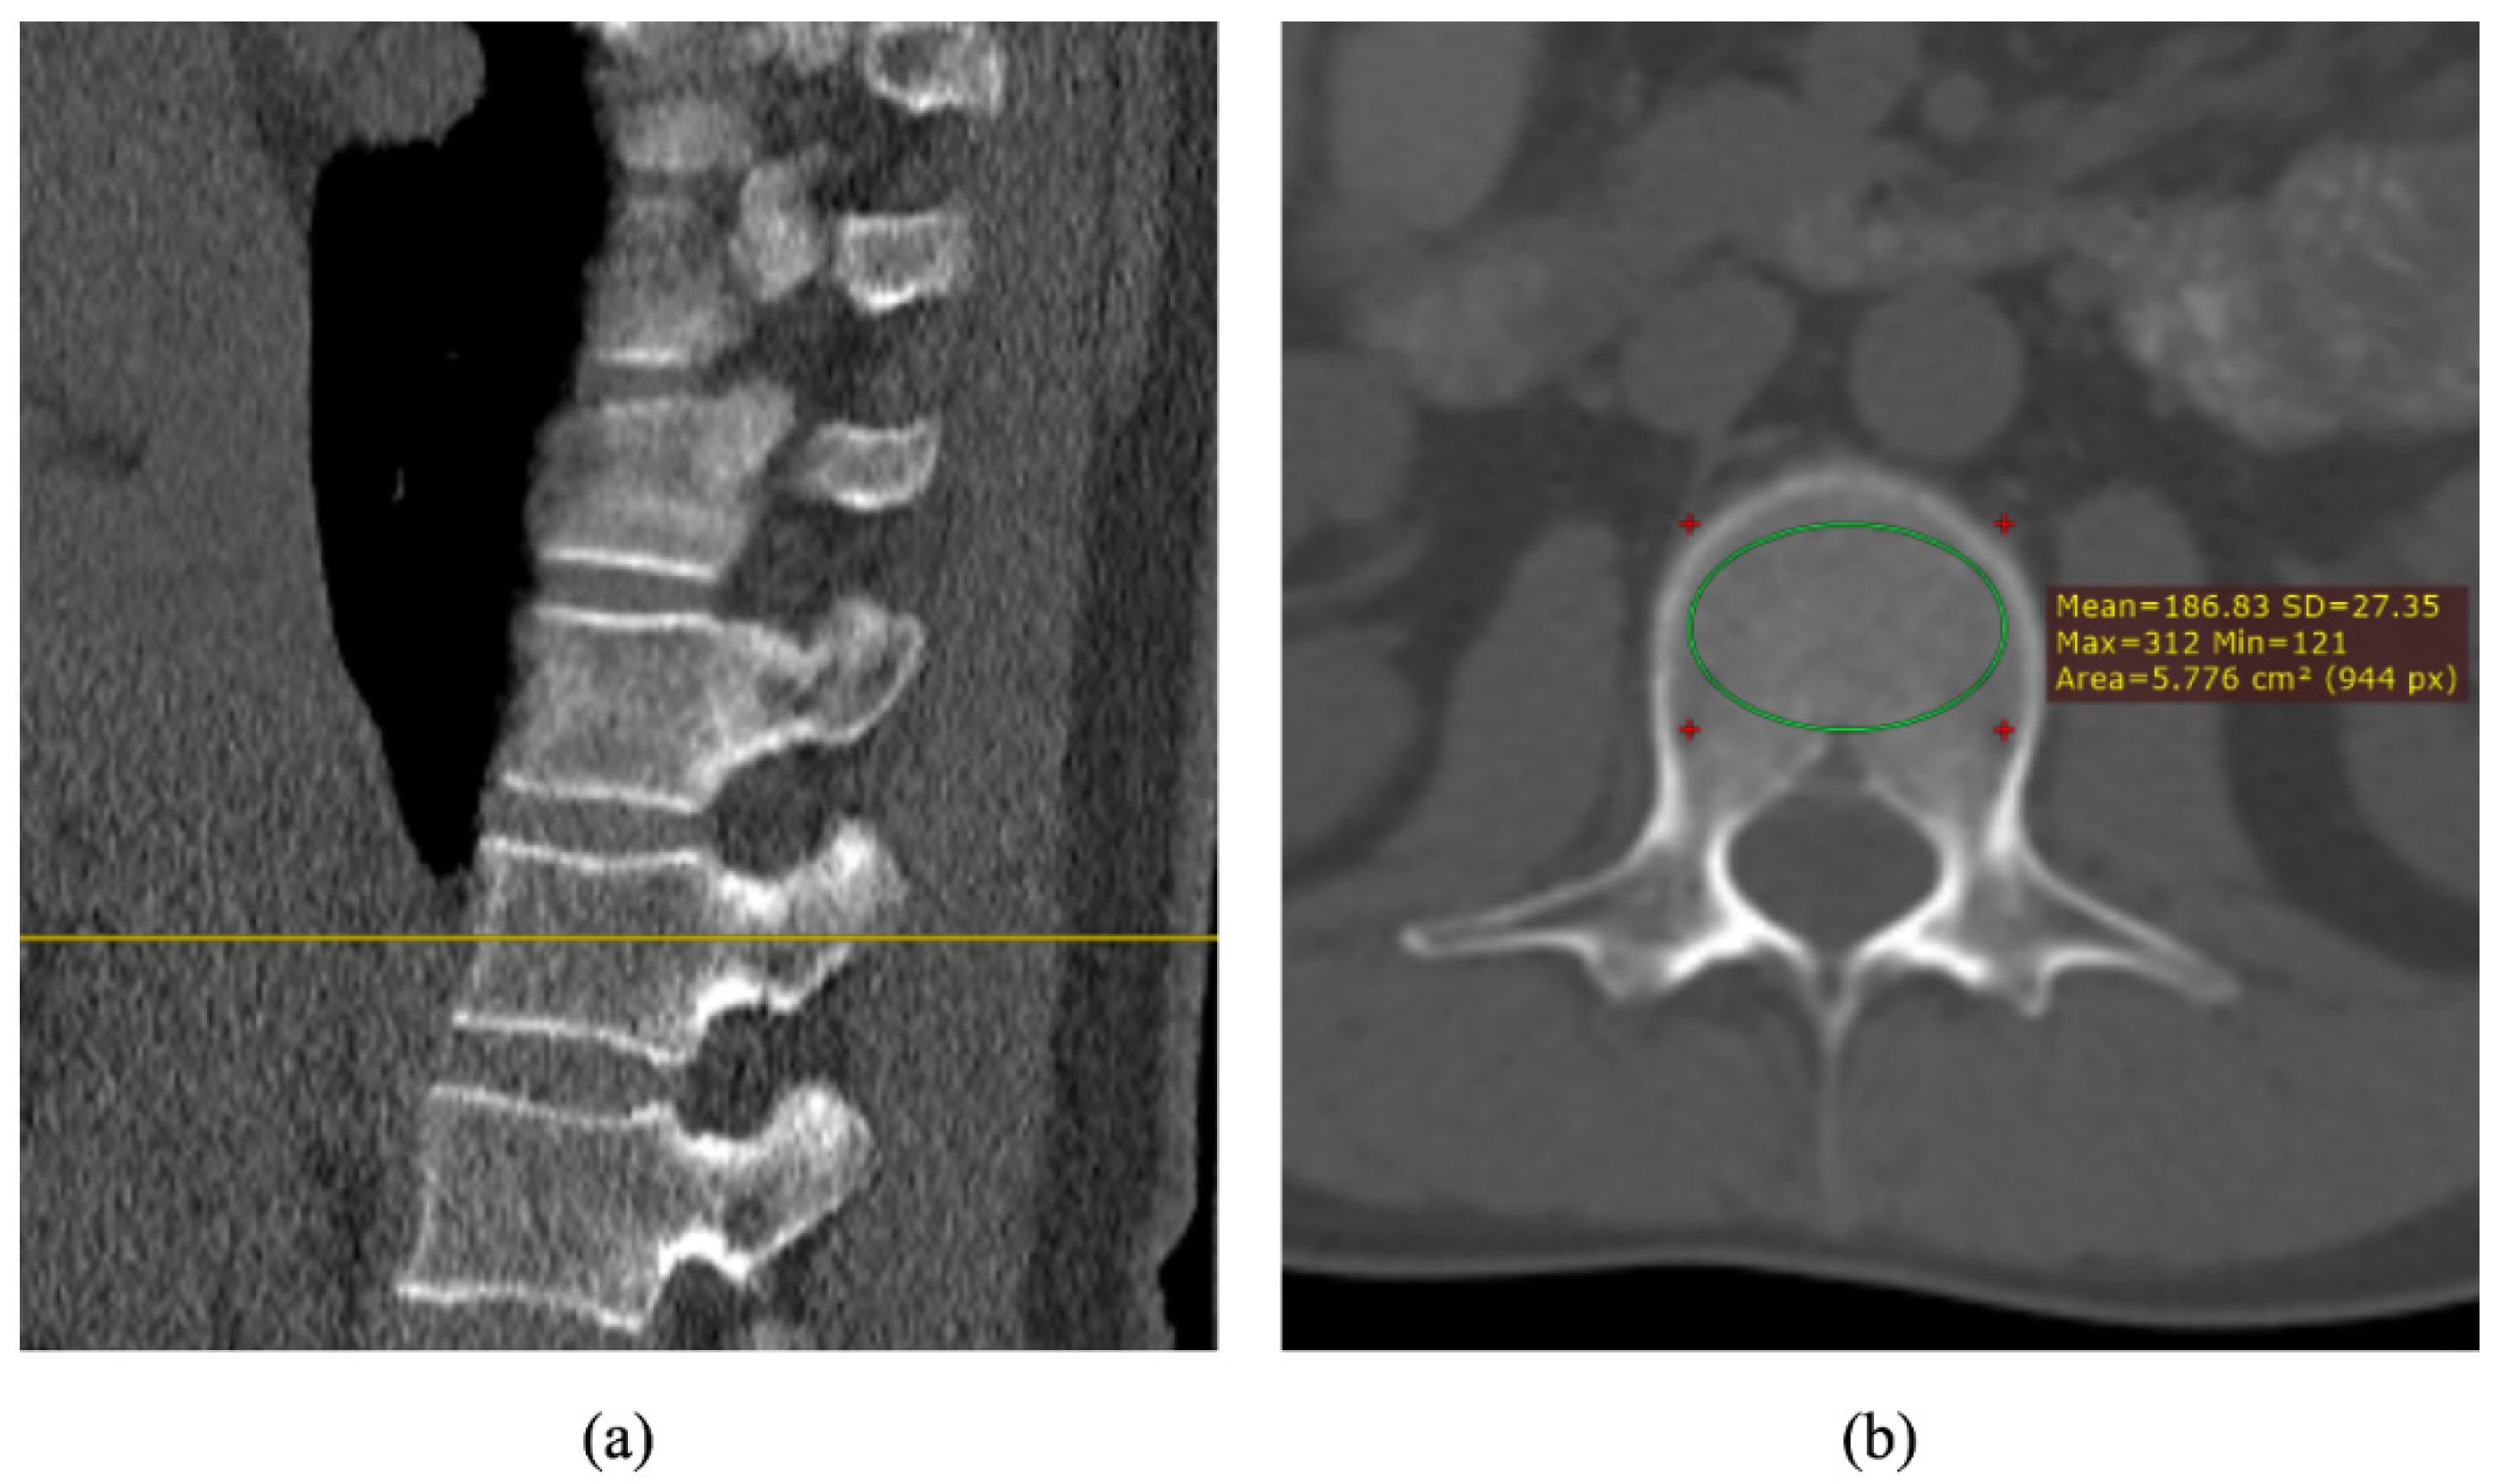

2.5. Analysis of CT Images